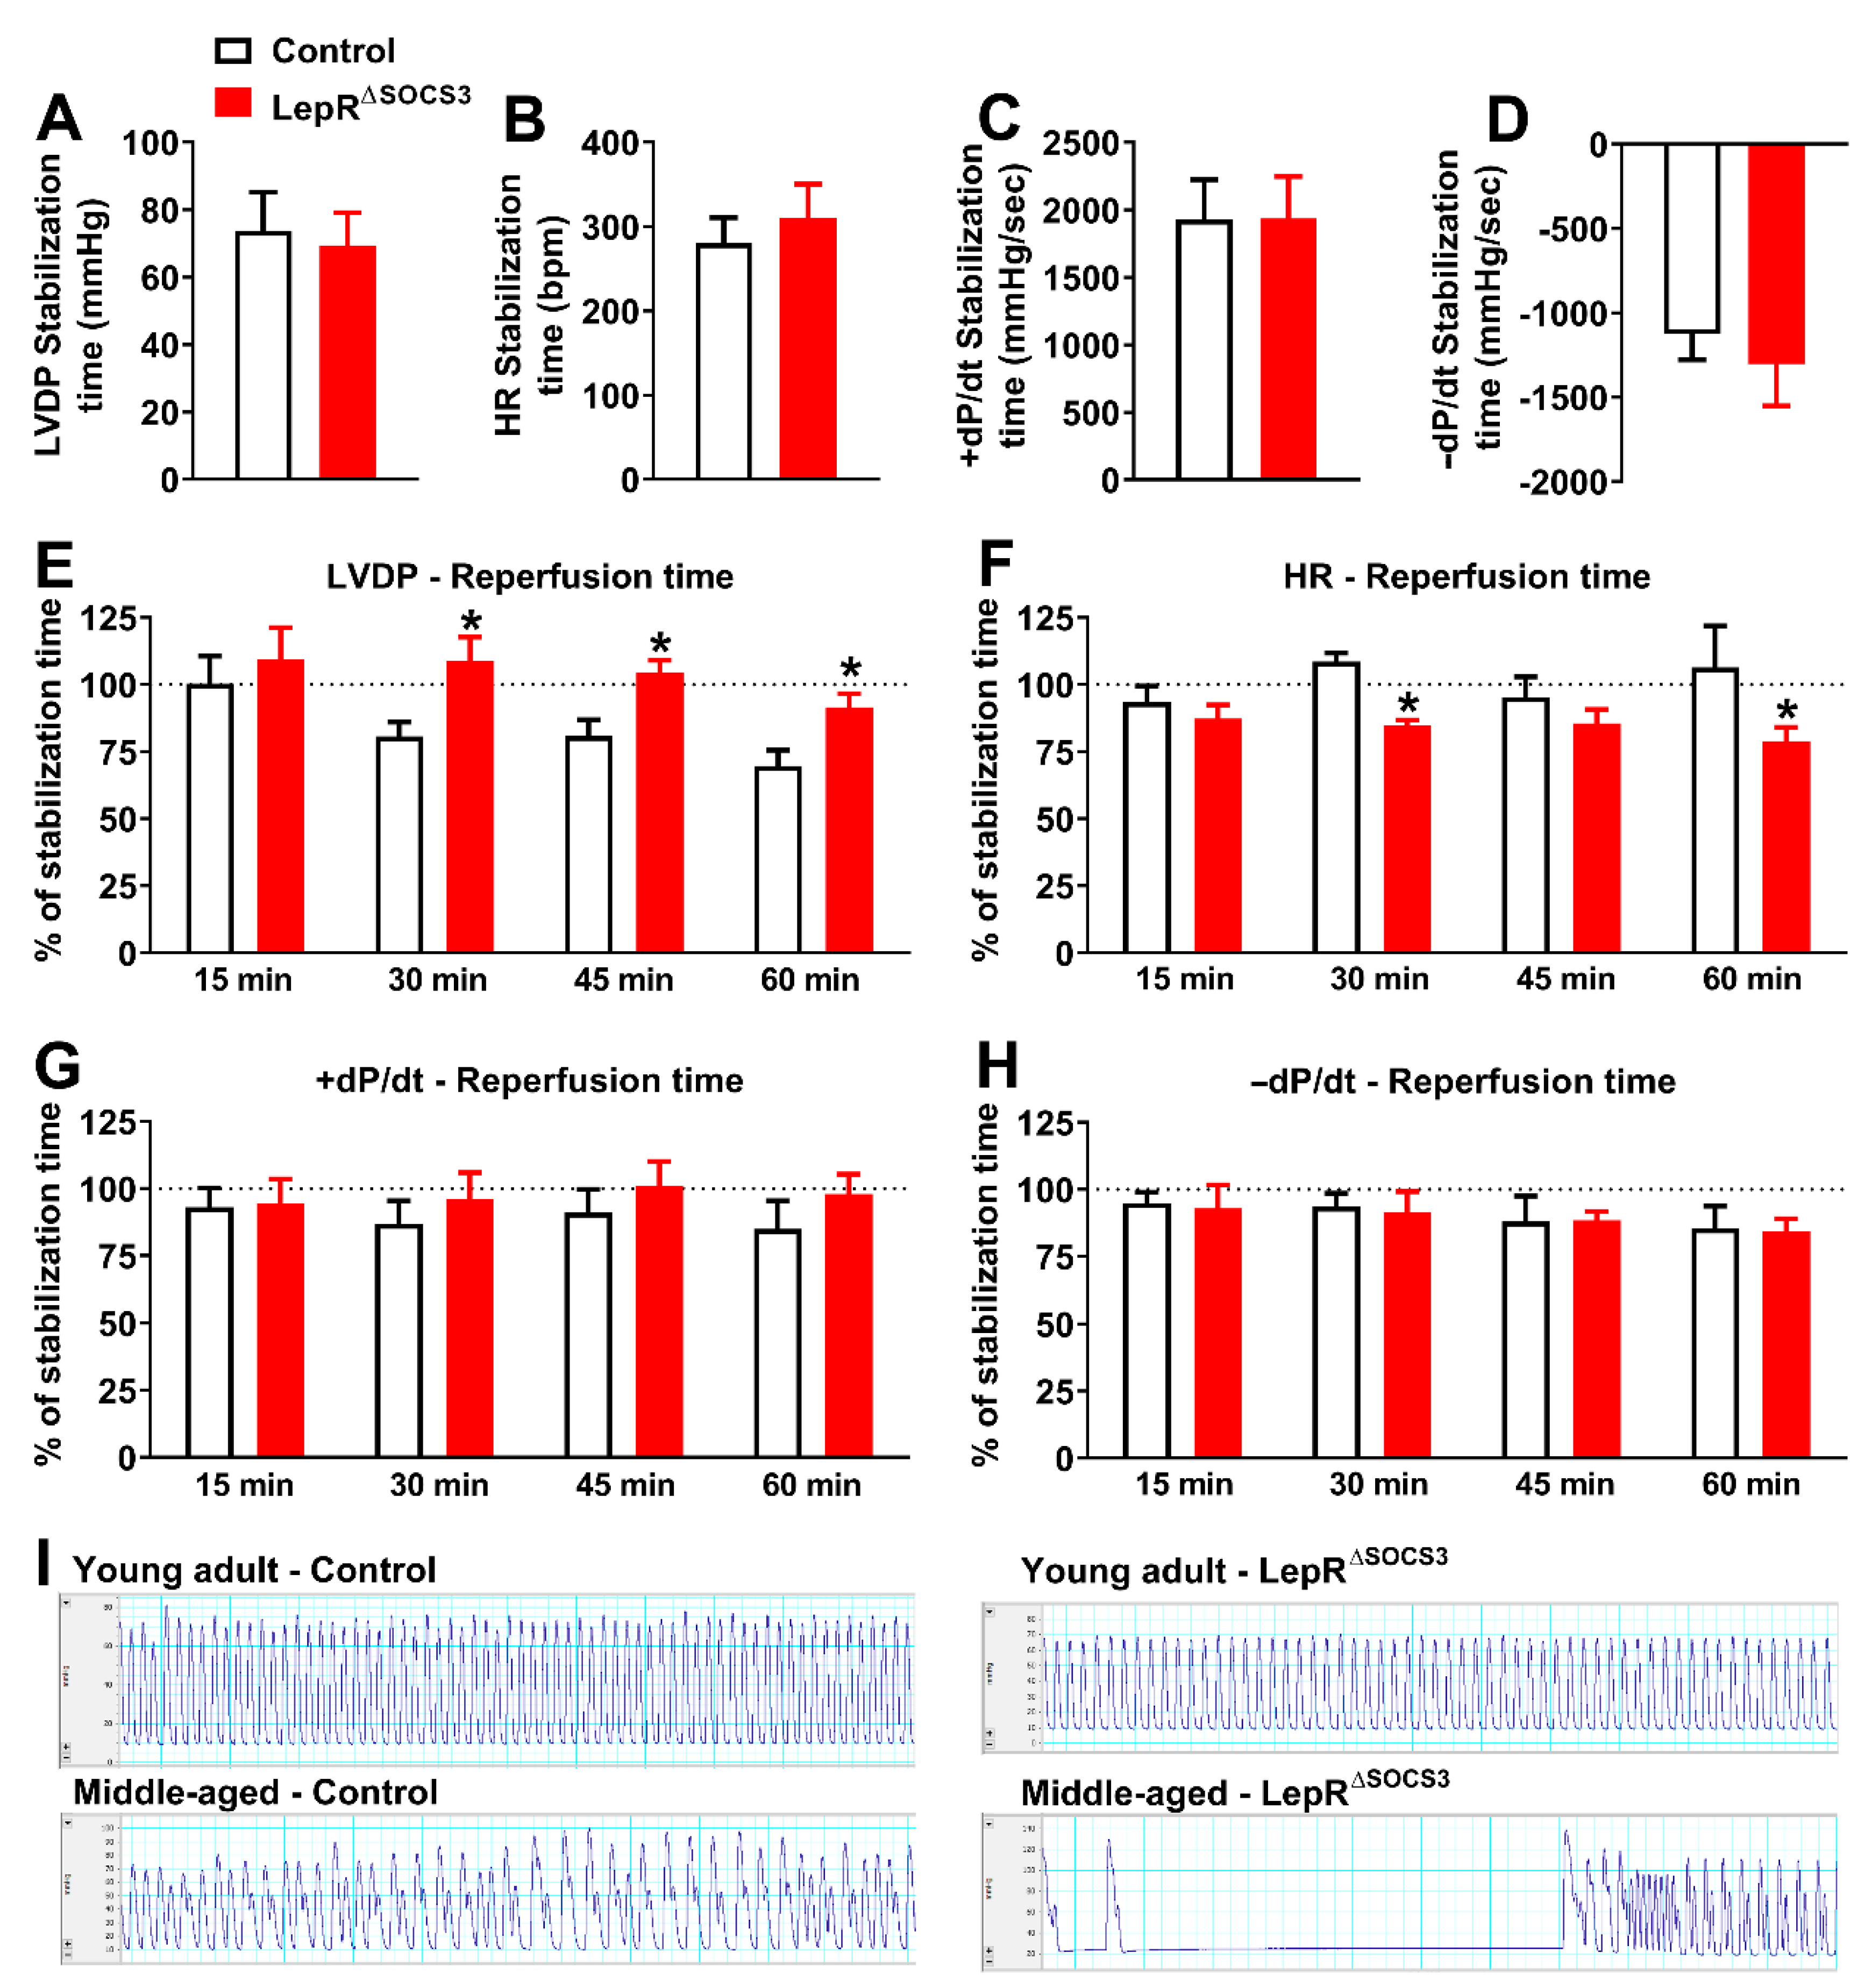

2.3. Cardiac Abnormalities and Decreased Survival Rate in Aging LepR∆SOCS3 Mice

4.6. Constant Flow Langendorff Preparation